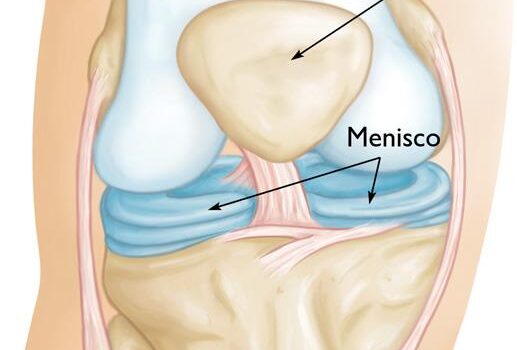

Antes de mais nada, a cirurgia de menisco representa uma das soluções mais indicadas para pacientes que sofrem com lesões no joelho e não obtêm melhora com tratamentos conservadores. Dessa forma, o procedimento devolve mobilidade, reduz a dor e permite que a articulação volte a funcionar de maneira eficiente. Quando […]

Antes de mais nada, a artroscopia no joelho representa uma técnica moderna e minimamente invasiva que auxilia no diagnóstico e tratamento de diferentes lesões articulares. Dessa forma, pacientes que sofrem com dores persistentes, inflamações ou limitações de movimento encontram nesse procedimento uma alternativa segura e eficaz. Indicações da artroscopia no […]